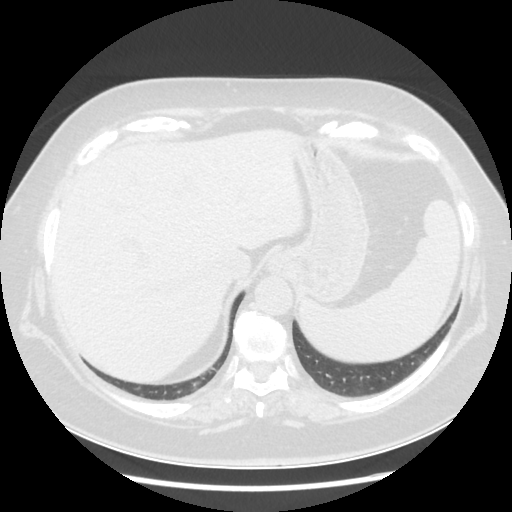

Generated VENOUS CT scan (A→B translation)

Full window (WL 1023.5, WW 4095 β†’ Low βˆ’1024, High +3071)

Actual HU range: [-1024.0, 981.6]

Lung window (WL -600, WW 1500 β†’ Low βˆ’1350, High +150)

Actual HU range: [-1350.0, 150.0]

Mediastinum window (WL 40, WW 400 β†’ Low βˆ’160, High +240)

Actual HU range: [-160.0, 240.0]